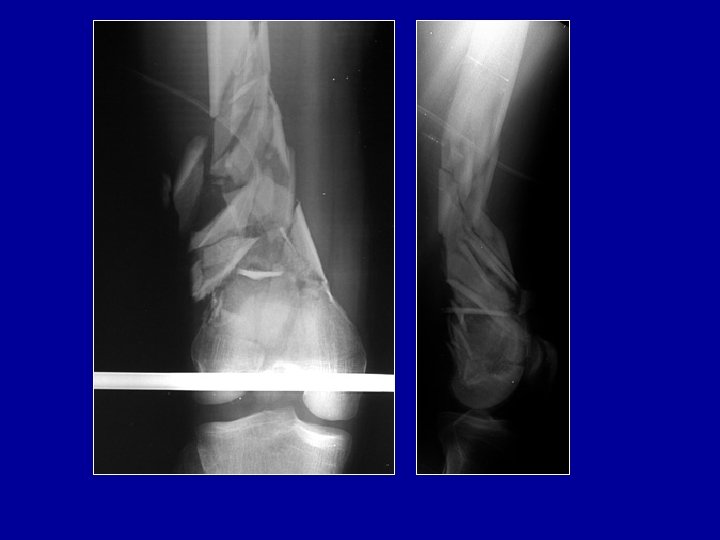

Cas particulier des fractures métaphysaires ouvertes Les broches sont difficiles à placer dans une épiphyse

Cas particulier des fractures métaphysaires ouvertes Les broches sont difficiles à placer dans une épiphyse Fixateur de Sheffield

Cas particulier des fractures métaphysaires ouvertes Ostéosynthèse a minima de l’épiphyse et de la métaphyse et mise en place d’un fixateur à distance

Cas particulier des fractures métaphysaires ouvertes Ostéosynthèse a minima de l’épiphyse et mise en place d’un fixateur. Quand le péroné est déplacé, une plaque est possible si la peau est intacte en dehors En cas de perte de substance osseuse, on fera une greffe secondairement

Cas particulier des fractures métaphysaires ouvertes